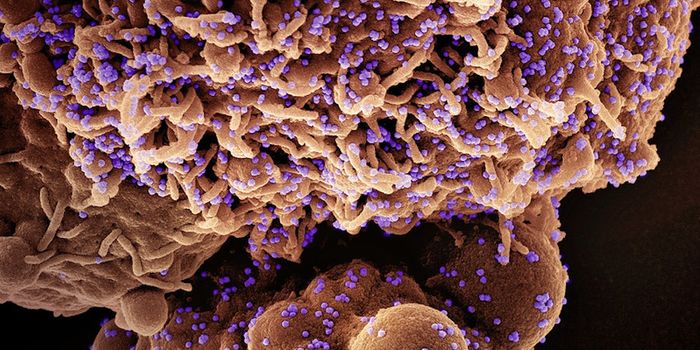

AUG 24, 2020ImmunologyOnce in the body, HIV tracks down T cells that bear the CD4 receptor. It attaches to these immune cells, fusing itself w ...